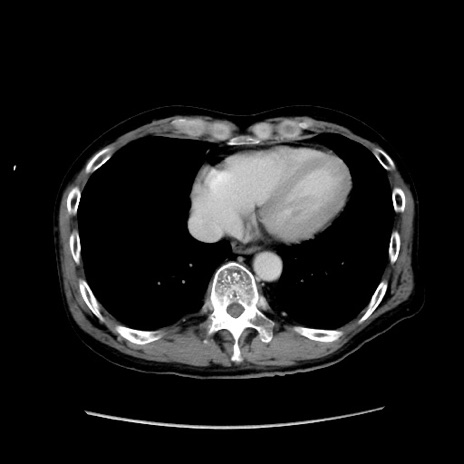

症例37(横断像)

【症例】40歳代 男性

【主訴】腹痛

【現病歴】4時間ほど前に電車に乗車中に臍部上より腹痛出現。徐々に増悪し起立困難となり、救急外来受診。生ものは数日食べていない。今朝お雑煮を食べた。

【身体所見】BT 36.8℃、BP 117/84mmHg、HR 91/min、SpO2 97%、苦悶様、腹部:臍上部広範囲圧痛あり、反跳痛±

【データ】WBC 8100、CRP 0.03